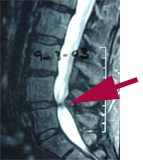

Spinal stenosis is a common back pain diagnosis especially in older folks. The chiropractic technique Aurora Chiropractic Center uses is called Cox® Technic Flexion Distraction. It is shown to be more effective than other conservative therapies to reduce pain and disability. (1) Experience the relief for yourself at your next Juneau chiropractic visit!